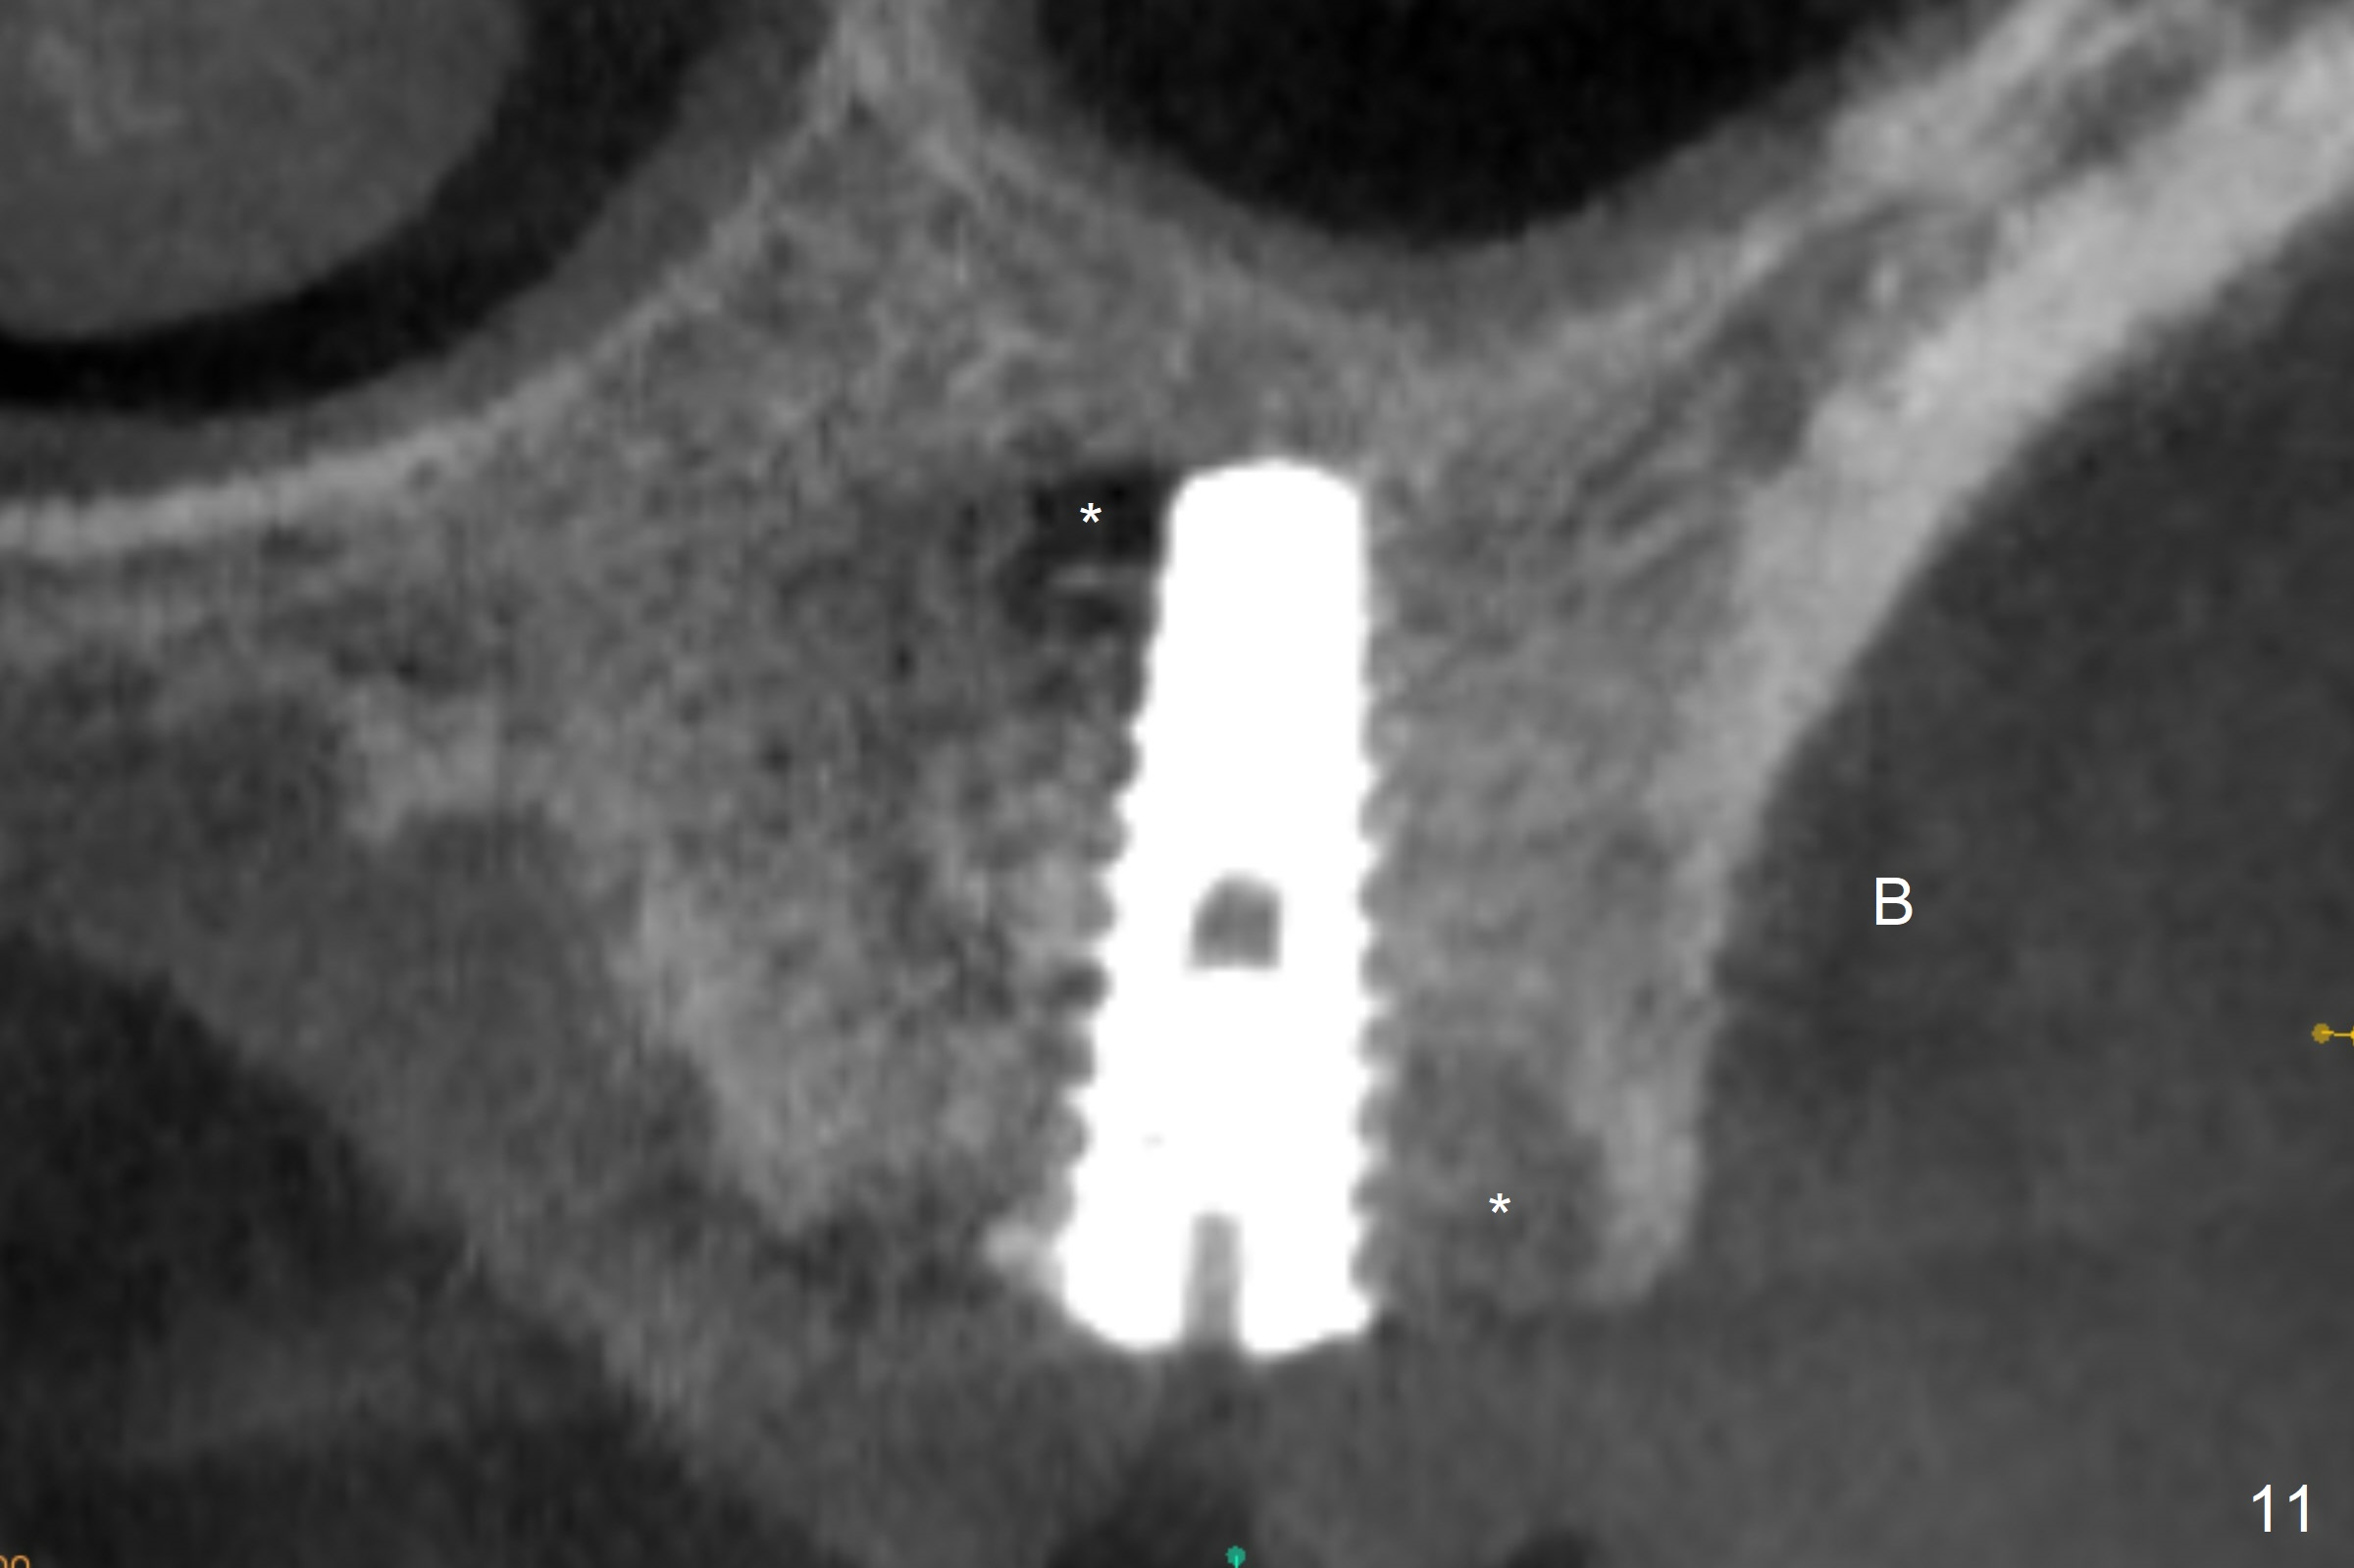

The amount of the bone graft mesial and distal the implant seems to reduce 3 and 4 months postop, respectively (Fig.6,7 arrowheads). When the acrylic is cut off 4 months postop, the bone graft is loose. The gingiva is unhealthy. The abutment and implant are loose. A healing abutment is placed (5x4 mm). The implant is torqued to 35 Ncm 6 months postop with the healing abutment reapplied. The patient will return for follow up nearly 9 months postop. A larger healing abutment will be used if the implant is stable. Two weeks later, use a smaller restorative abutment for easy impression. In fact the implant is unstable with #15 mesial shift due to abnormal occlusion with #17 (Fig.8). Bone density around the implant is low (* in Fig.9 (PA), 10,11 (CT sagittal, coronal sections)). A healing screw is placed for self healing. A 2nd option is to remove the implant (Fig.12), BEB (Fig.13) and place the implant deeper (Fig.14) or larger one (5.5-6.5x13 mm). The 3rd option is to place larger and longer implants (Fig.15 (tapered), 16 (cylindrical)). The implant access has partially closed 14 months postop, but there is a small buccal opening with sanguine exudate. Incision reveals severe bone loss around the implant; the mobile tooth #15 is extracted (Fig.17). After debridement and irrigation with normal saline, Vera Graft (Fig.18 *) and Collagen plug are placed with periodontal dressing.